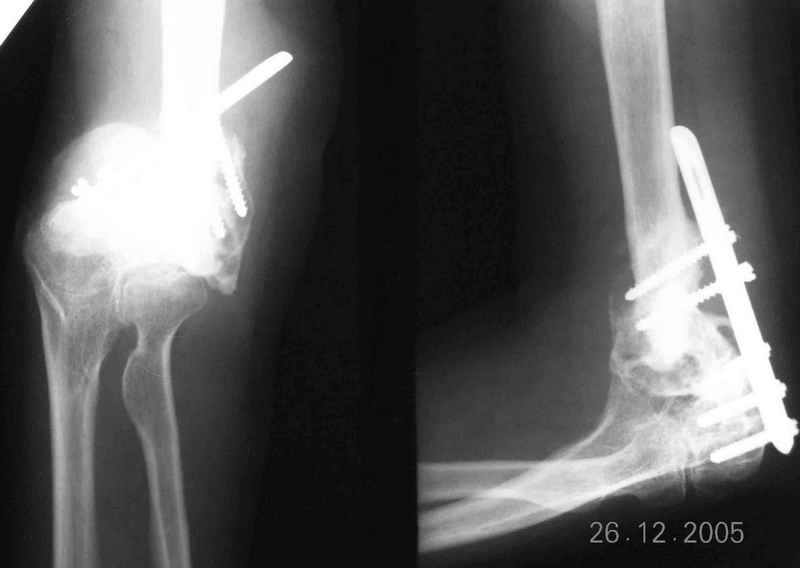

The recent x rays show established Non union with poor quality bone in the distal fragement. The joint is also appearing degenerate. In view of the multiple failed reconstructive surgeries, an Elbow replacement would seem reasonable.

However it would have to be a fully constrained one as there would be missing bone stock.